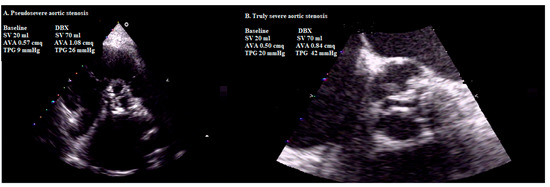

4.1. Dobutamine Stress Echocardiographic